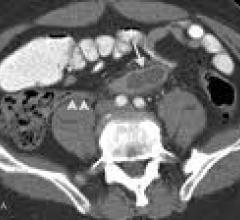

Computed tomography (CT) systems use a series of X-ray images to create an image volume dataset with slices that can be manipulated on any plane using advanced visualization software. The section includes computed tomography scanners, CT contrast agents, CT angiography (CTA and CCTA), CT perfusion, spectral CT (dual-source CT), and iterative reconstruction dose reduction software.

July 20, 2010 – New dual source CT technology allows a radiation dose of as low as one millisievert (mSv) for computed ...

July 20, 2010 – Researchers at the Mayo Clinic have developed a way to reduce the amount of radiation involved in ...